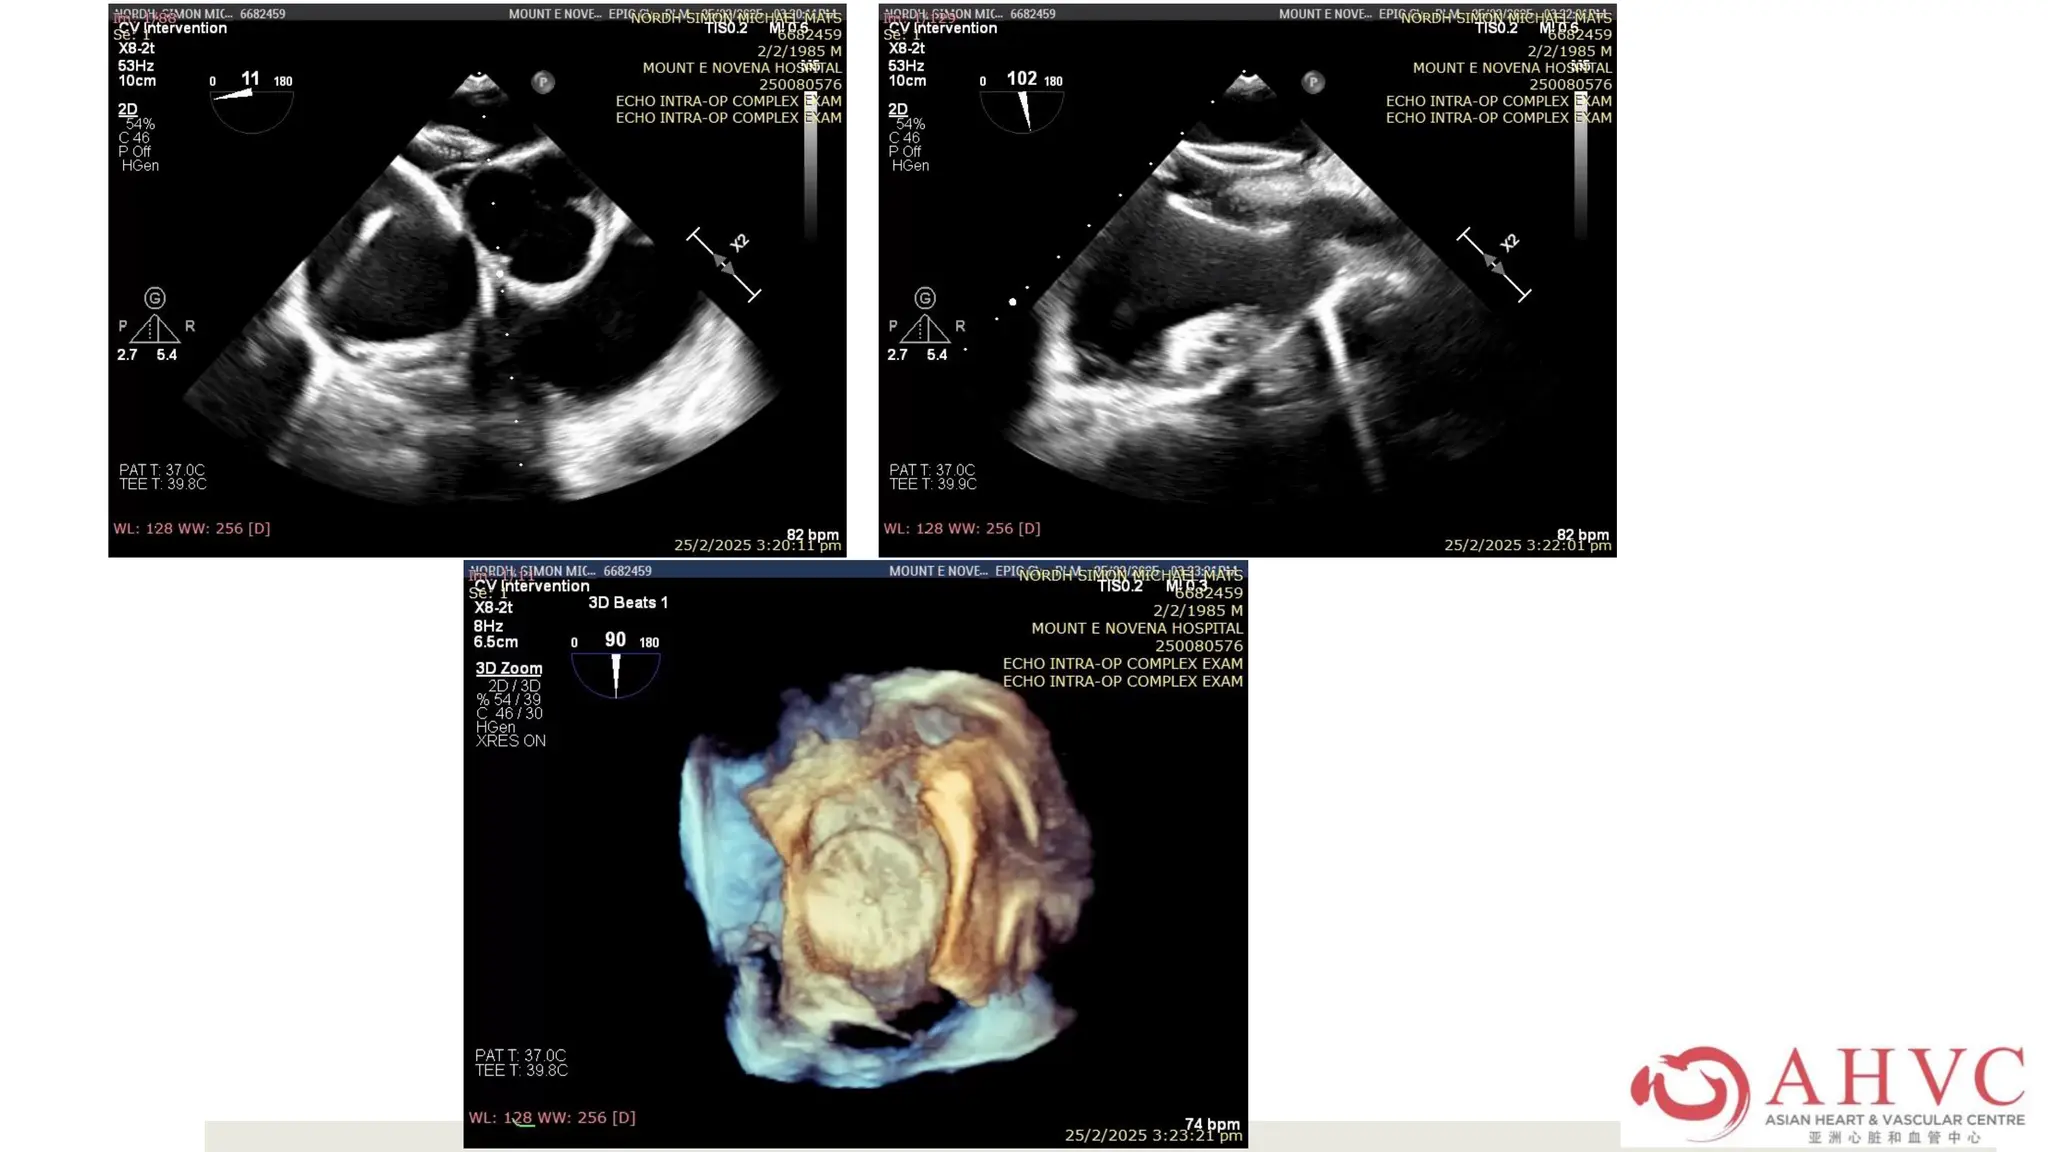

Case – Mr CKK

He was planned for EPS ablation

in July 2021.

CTCA done in June showed

minor CAD and no LAA clot.

His Xarelto was stopped for 1

day and he had TEE prior to EPS.

New LAA clot.

Case – MrCKK He was planned for EPS ablation in July 2021. CTCA done in June showed minor CAD and no LAA clot. His Xarelto was stopped for 1 day and he had TEE prior to EPS. New LAA clot.

Case – MrCKK After LMWH for 6 weeks, he came back for EPS AF in Dec 2021 and had successful PVI. He was in paroxysmal AF post ablation but his NYHA improved. In April 2022, he had recurrence of persistent AF. He was admitted for cardioversion.

Case – MrCKK TEE was done before cardioversion which showed no clot in LAA. His Lixiana was uninterrupted.